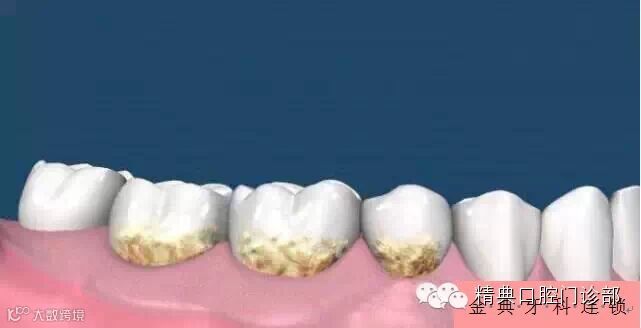

图片二、时间长了,您的牙面上滋生牙菌斑和牙结石。

图片三、当牙菌斑和牙结石累计一定程度时,牙龈开始变得红肿。